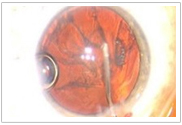

手術(shù)醫(yī)生可以在手術(shù)過程中監(jiān)視全部眼前節(jié)

(1)高分辨率的視頻顯微鏡,實時成像

(2)一體化的、廣角的光學相干斷層

掃描(OCT),三維成像